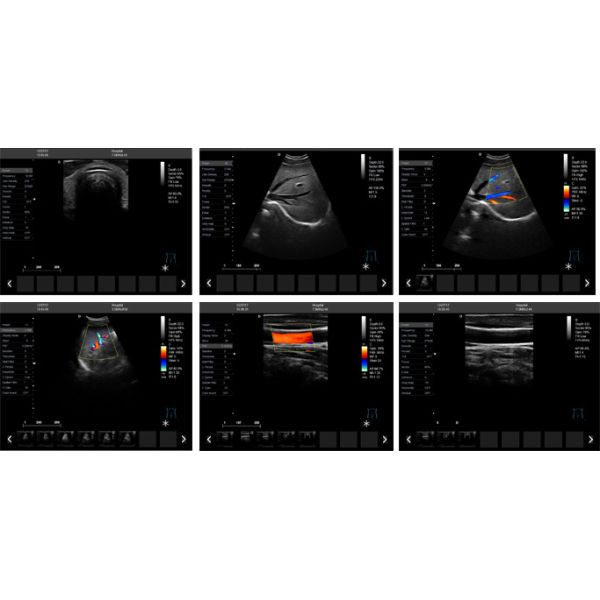

LAPTOP COLOR DOPPLER ULTRASONIC SYSTEM

Laptop color doppler Ultrasound Diagnostic Syste... Images |